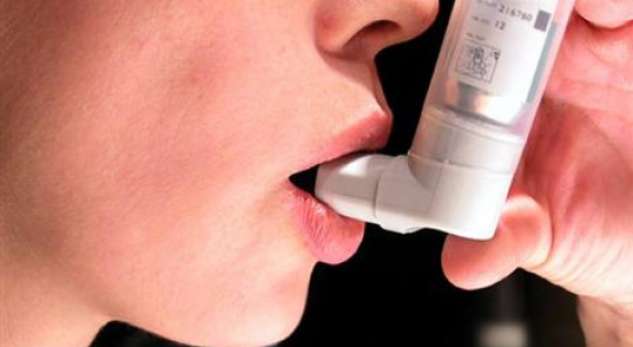

Mbi 25 milion amerikanë kanë astmë, një sëmundje kronike e shkaktuar nga inflamacioni në tubat bronkial, ose rrugët e frymëmarrjes, në mushkëri. Njerëzit me astmë të vazhdueshme marrin ilaçe kontrolluese të përditshme për të mbrojtur rrugët e frymëmarrjes nga shtrëngimi dhe për të parandaluar kollitjen, frymëmarrjen, gulçimin ose shtrëngimin e gjoksit. Pacientët dhe mjekët duhet të dinë për lidhjen midis astmës dhe AFib, tha Dr. Marc Miller, një elektrofiziolog kardiak dhe një asistent profesor i kardiologjisë në Icahn School of Medicine në Mount Sinai në Neë York City. Por ai paralajmëroi se studimi nuk tregon se astma po shkakton AFib.